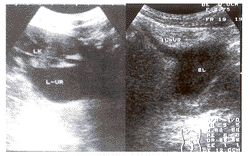

超声诊断先天性肾旋转反常并巨输尿管及其开口位置异常1例

患者男, 14岁 ......